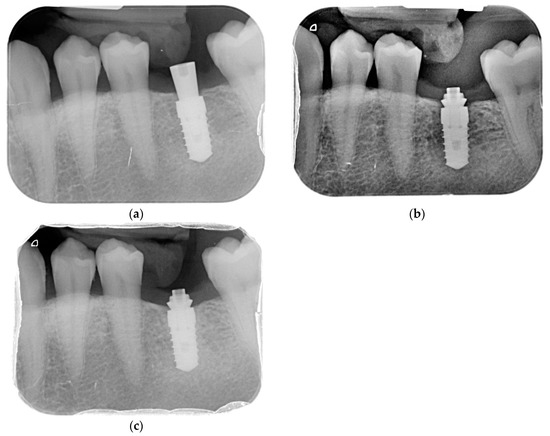

To evaluate interproximal bone levels, (individualized bite holder) standardized intra-oral radiographs were performed using the long-cone paralleling technique. The radiographs were taken before implant placement, postoperatively, at 2, 6, and 12 months—see Figure 2.

Figure 2. Case evolution. (a) Rx Baseline; (b) Rx 6 M; (c) Rx 12 M.